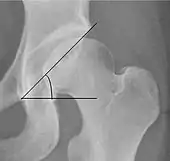

| Sharp angle | ![]() |

Acetabular slope | <45°

|